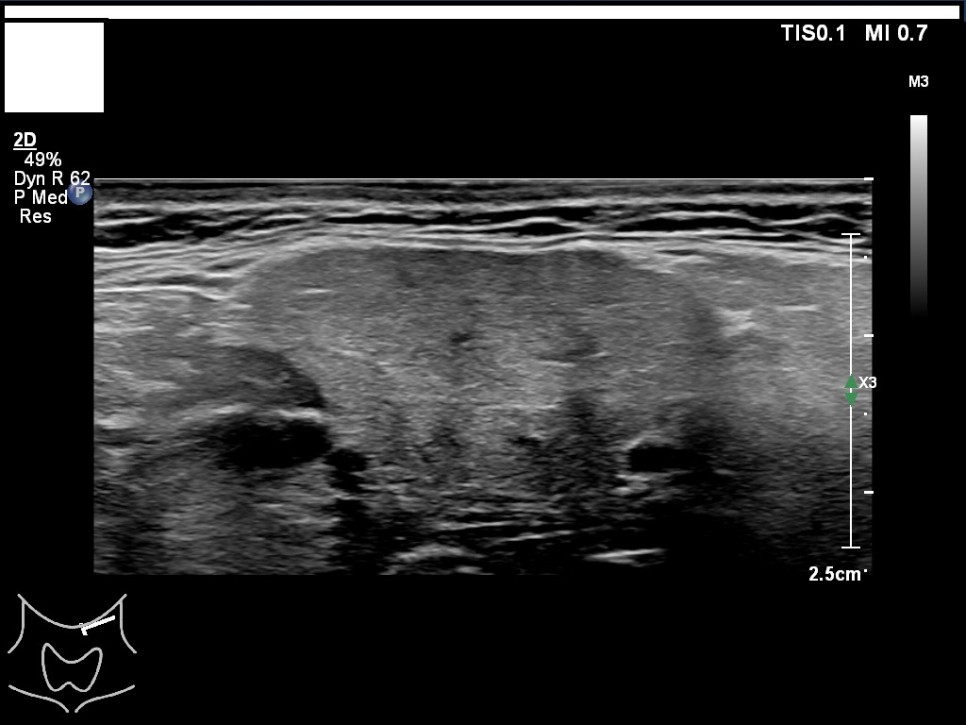

갑상선, 부갑상선 초음파 검사 급여 기준 1. 표준 영상의 범위 모든 영상에는 경부의 해부학적 위치(모식도나 문자)를 표기하여야 한다.

A) 병변이 없는 경우: 우엽 중부 가로 스캔, 우엽 중앙부 세로 스캔, 협부 가로 스캔, 좌엽 중부 가로 스캔, 좌엽 중앙부 세로 스캔, 우경부 림프절, 좌경부 림프절 나) 병변이 있는 경우: 병변이 없는 경우의 표준 영상과 함께 병변 부위에서 2개의 수직 관계 단면 영상(횡단/종단) 및 병변의 크기가 측정된 경우: 병변이 없는 경우의 표준 영상

좌경부 림프절 5/우엽 중부 가로 스캔/우엽 중앙부 세로 스캔

우경부림프절/좌엽중앙세로 스캔/좌엽중앙가로스캔